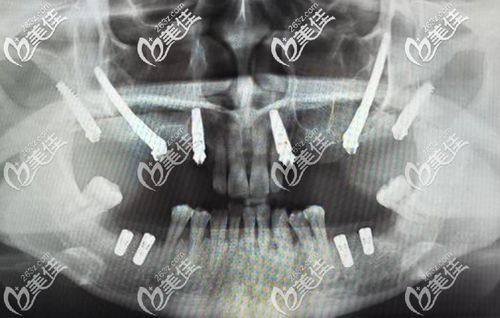

口腔种植:可开展韩国SG、奥齿泰、皓圣等多种品牌种植体项目,能完成all-on-4、穿颧穿翼等高难度种植,依托全数字化诊疗技术实现精细微创种植,术后修复快,适配不同缺牙患者的个性化需求。

许俊豪(业务院长):空军军 医 大学口腔医学学士,获北京市口腔医学会《杰出口腔医师奖》,擅长口腔颌面外科修复技术、微创微痛种植牙技术、老年人疑难义齿修复及拔除,成功解决上千例口腔疑难杂症,可开展复杂颌面外科手术及高难度微创种植牙手术。